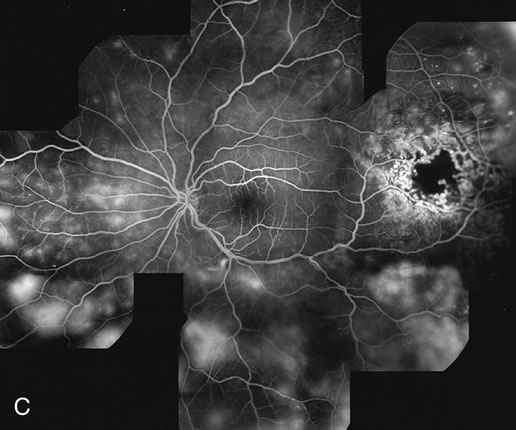

Clinically discernible peripheral dependent bullous neurosensory detachments have been described in patients with chronic CSC.85–92 Yannuzzi and co-workers first characterized the presence of RPE atrophic tracts extending inferiorly in the fundus periphery secondary to antecedent retinal detachment in patients with CSC.85 Presumably, there is a particularly severe and/or longstanding leakage of fluid from an RPE defect in the subretinal space at the posterior pole. The subretinal fluid gravitates inferiorly to form a dependent neurosensory detachment in a “flask,” “teardrop,” “dumbbell,” or “hourglass” pattern (Fig. 31). Sometimes the tract of subretinal fluid connecting the macular detachment with the bullous neurosensory detachment in the inferior hemisphere is so shallow that it is very difficult to appreciate. The RPE under the chronic retinal detachment experiences atrophic changes that appear as atrophic RPE tracts connecting the posterior pole with the dependent retinal detachment. The retina itself develops secondary manifestations including pigment migration, capillary dilatation (telangiectasia) proximally and capillary nonperfusion (ischemia) distally to the area of detached retina (see Fig. 31). The changes in the RPE consist of both RPE atrophy and pigment clumping in the form of perivascular deposits or bone spicules, a condition described by Gass as a “pseudoretinitis pigmentosa–like atypical CSC presentation.”87

Fig. 31. A 47-year-old woman with an18-year history of central serous chorioretinopathy in both eyes. A. Color photograph composite of the left eye shows bullous dependant detachment of the neurosensory retina inferiorly. B. Fluorescein angiogram composite reveals diffuse decompensation of the retinal pigment epithelium, multiple scattered pigment epithelium detachments 9PEDs), and obliteration of the retinal capillaries in the region of the detachments. Note the presence of early neovascularization at the junction between perfused and non-perfused retina. C. Clinical photograph of the left eye shows PED superior to the optic disc partially surrounded by fibrin deposits. D. Fluorescein angiography confirms the presence of active leakage from the serous PED. E, Color photograph composite of the same eye 2 months after laser treatment of the site of leakage reveals partial resolution of the detachment and lipid precipitation. F. Clinical photograph composite 16 months after the laser treatment in the area of the leakage shows complete resolution of the detachment and partial reperfusion of the inferior retina.